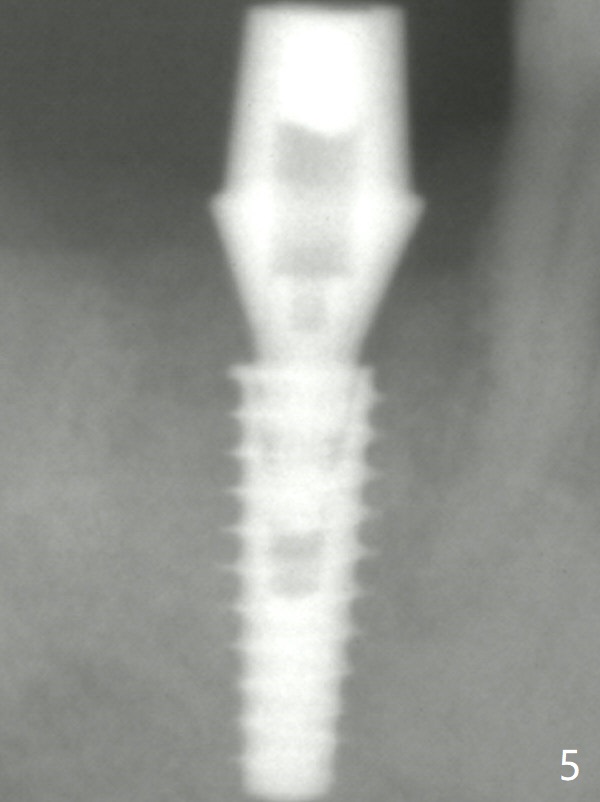

The definitive IBS implant (5x13 mm) is placed with 50 Ncm; a 6.5x5.7(4) mm abutment is placed with allograft filling the gap (* and arrow).

The final implant is placed a little too deep in this case. The problem can be avoided by using Tap with soft tissue depth mark and is solved by using a longer implant (5x13 mm) or having an abutment with longer cuff (5 or 6 mm). Postop there is tooth sensitivity. When the latter disappears, the patient feels the right jaw different. Panoramic X-ray taken 2 months postop shows that the implant has clearance from the Inferior Alveolar Canal (Fig.5 red dashed line). The mesial margin is subgingival. Laser gingivectomy is planned. Bone graft appears to remain in place.